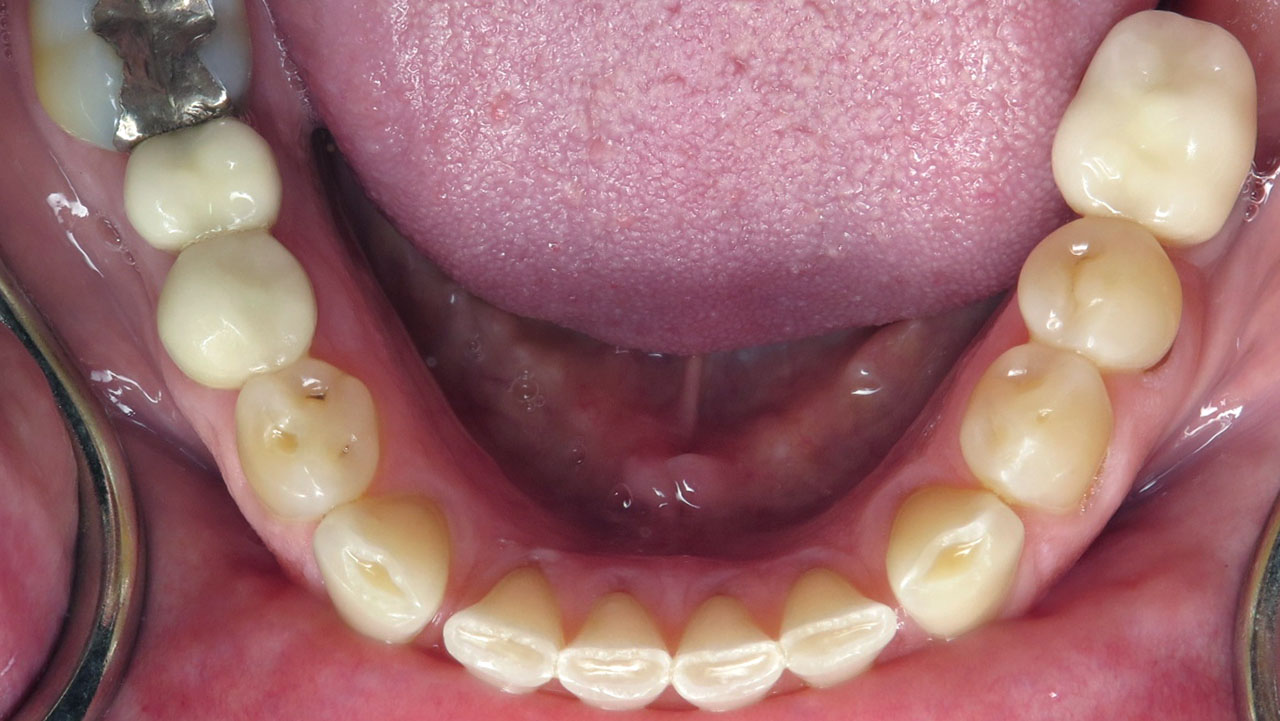

The patient had been diagnosed with sleep apnea and experienced severe tooth grinding. She noticed her front teeth becoming progressively thinner and sharper and was concerned about continued wear and damage.

Conservative composite bonding to rebuild and protect the worn edges of the upper and lower front teeth.

Composite bonding on seven upper teeth and eight lower teeth.

This patient had been diagnosed with sleep apnea and experienced significant tooth grinding. Although she wore a nightguard, she noticed she was also grinding during the day while working. Over time, the constant pressure had worn the edges of her front teeth very thin and sharp.

Instead, conservative bonding was used to rebuild the worn edges of the upper and lower front teeth. The treatment protected the exposed dentin and improved comfort and appearance while preserving future treatment options.